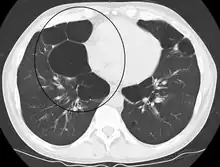

A severe case of bullous emphysema

Axial CT image of the lung of a person with end-stage bullous emphysema

Very severe emphysema with lung cancer on the left (CT scan)